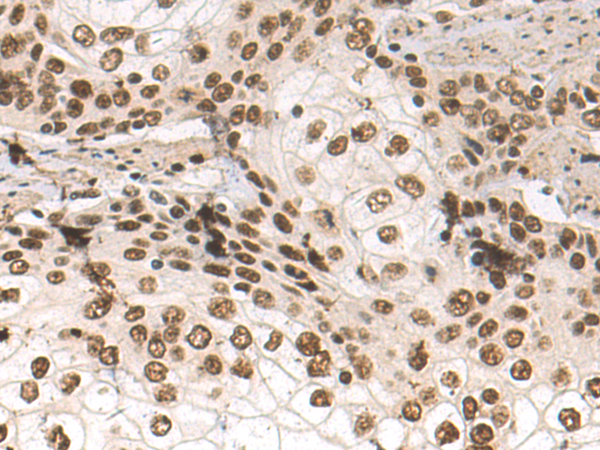

分类: 科研抗体货号: P10614别名: RIF; ARHF应用: WB,IHC反应种属: Human, Mouse